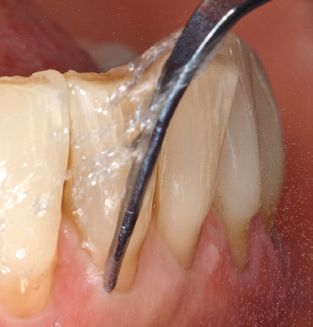

Following machine cleaning of the tooth and implant surfaces, the surfaces of the natural teeth are cleaned manually using standard hand instruments. When performing manual cleaning, particular attention must be given to maintaining the correct angle of application, appropriate sharpness, good support and working with the curette from apical to coronal. Either titanium or carbon curettes should be used for post-cleaning of the implant structures (Fig. 8). In addition to the use of ultrasonic devices, power jet devices can also be used in conservative dentistry. However, it must be taken into consideration that these procedures are not suitable for removing hard deposits and thus they cannot replace the use of hand instruments and ultrasonic instruments completely. In all cases, cleaning is followed by mechanical polishing of the accessible tooth and implant surfaces with polishing cups and polishing compounds (Fig. 9).